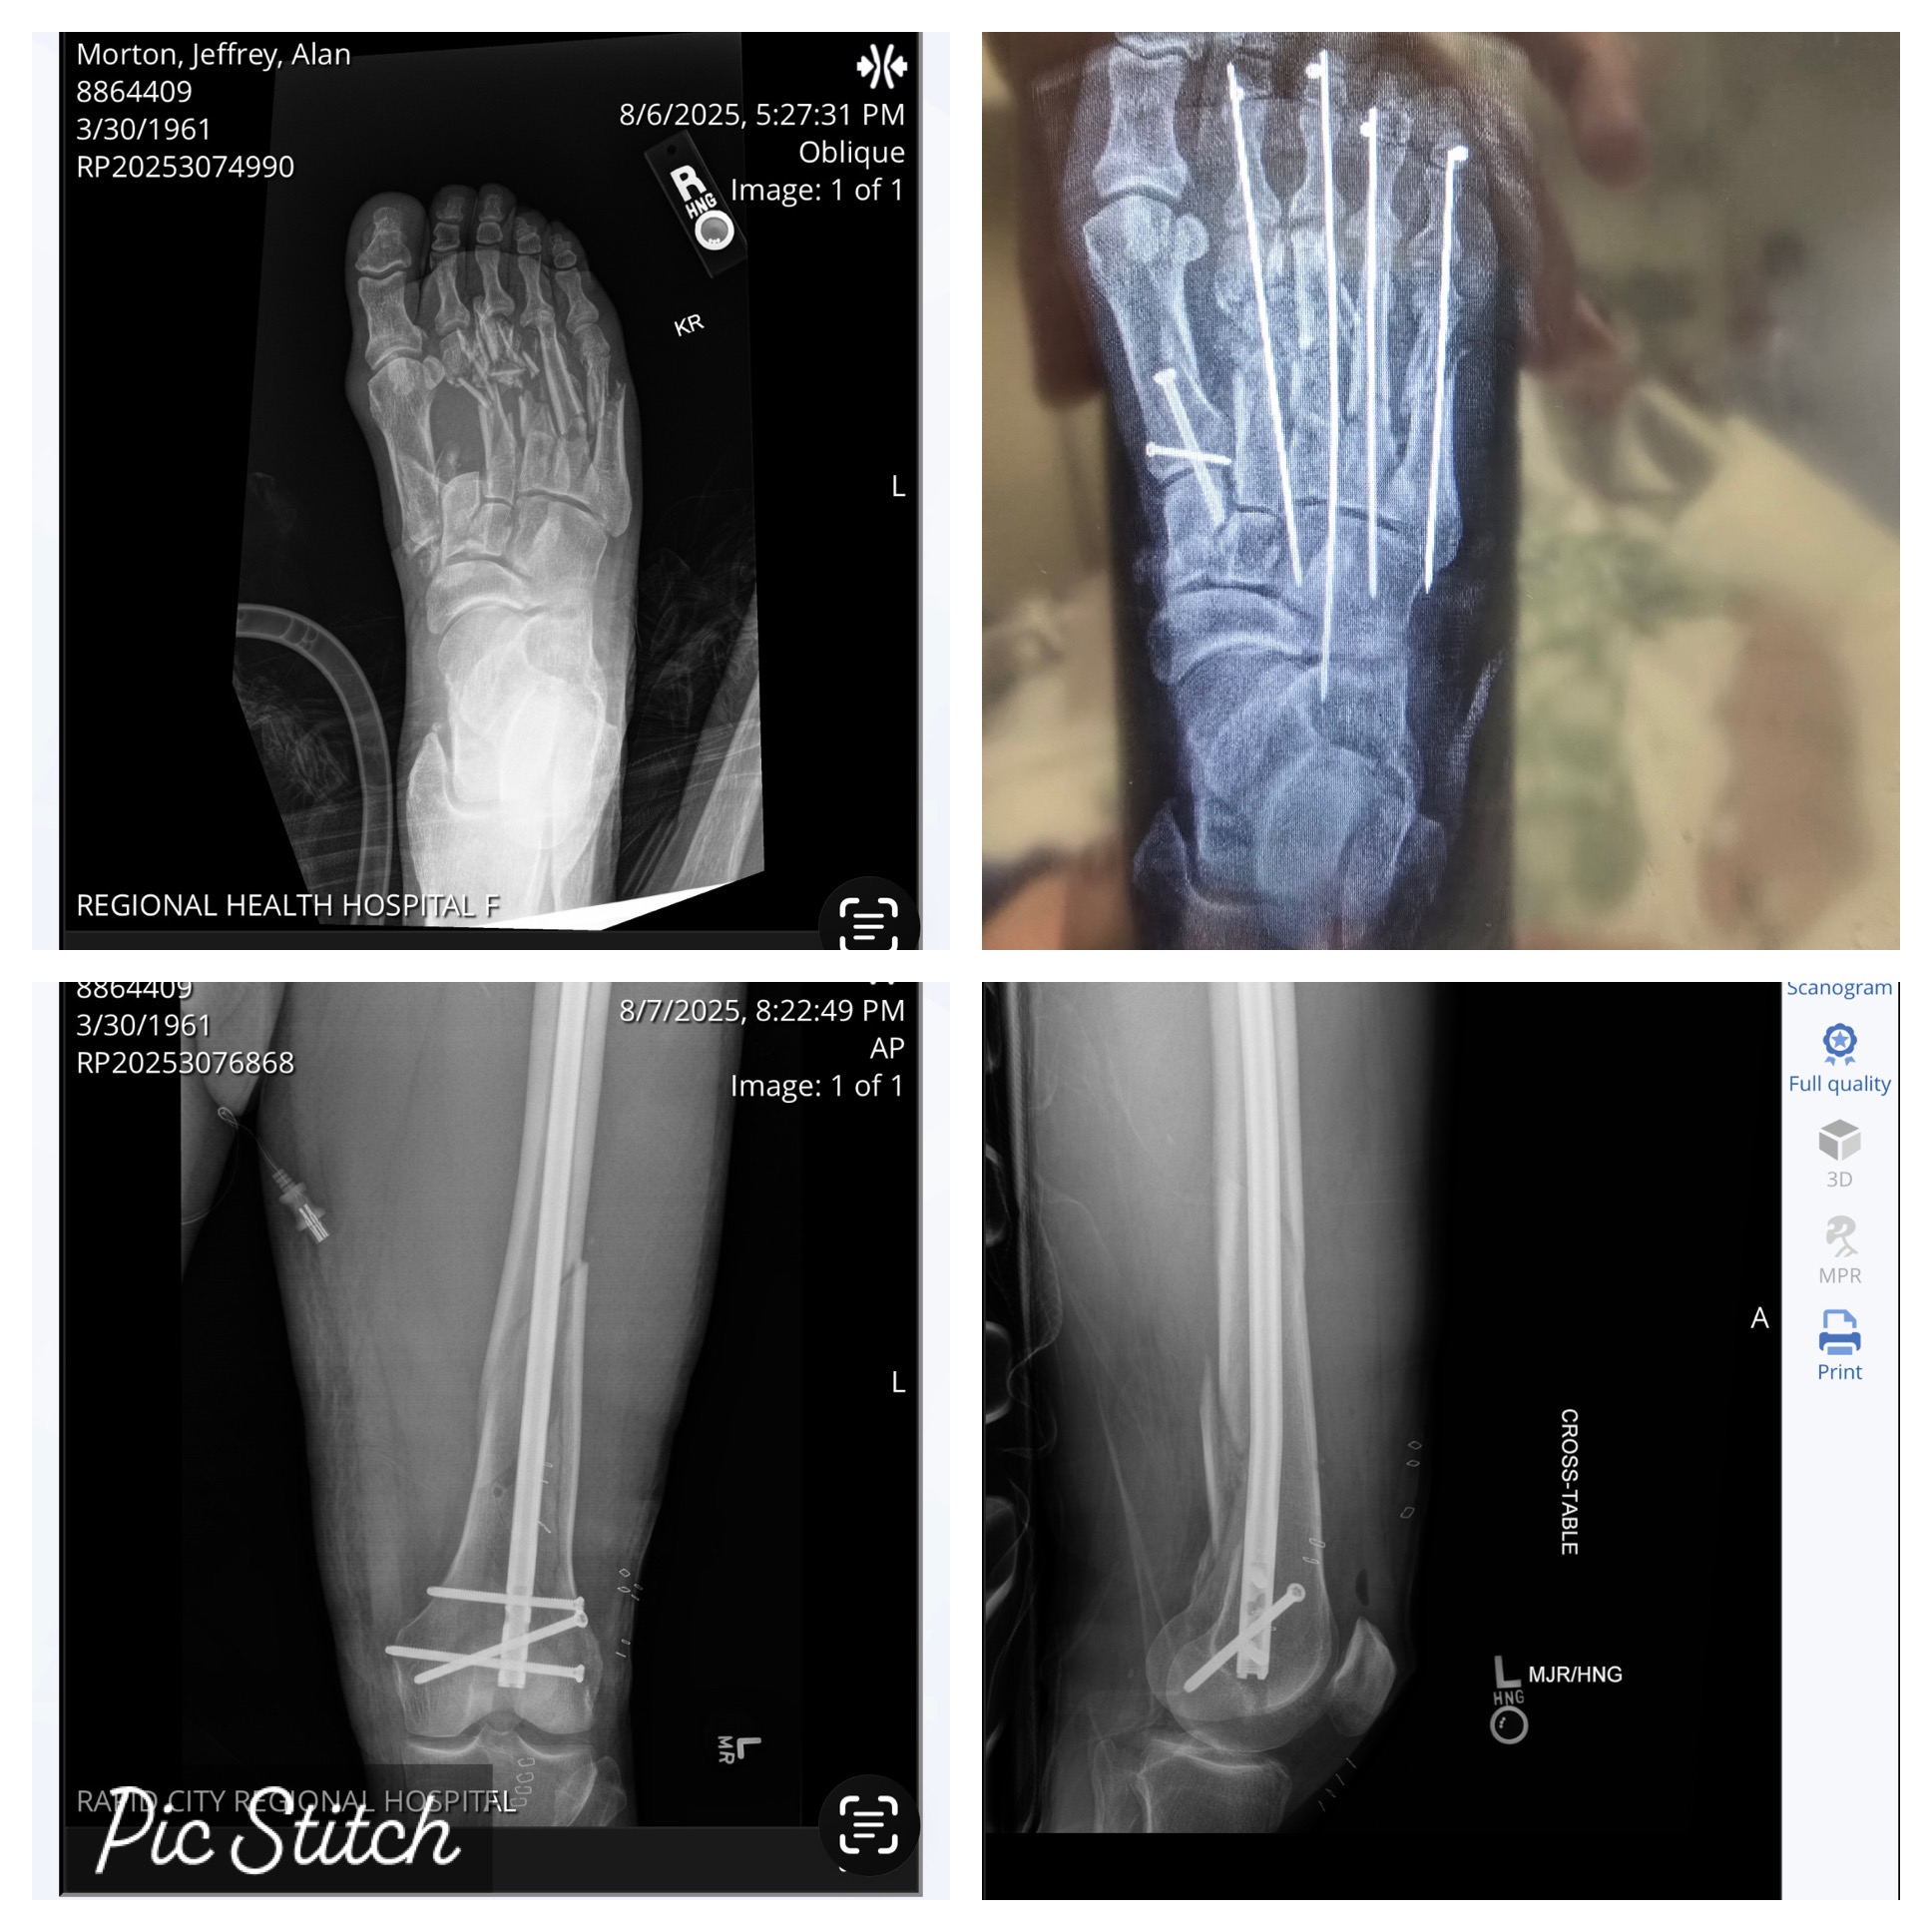

• Broken femur with a 17” rod.

• Multiple compound fractures on right foot crushing all four metatarsals requiring three reconstructive surgeries so far.